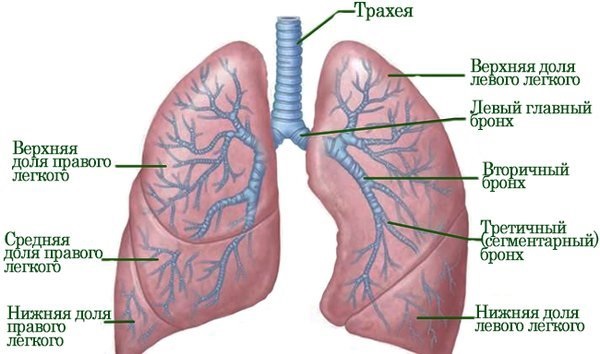

Различается болезнь и по расположению патологии в легких. Рубцовые ткани, растущие в нижнем участке, называются корневым фиброзом, в центральной части — базальным, в верхних областях — апикальным.